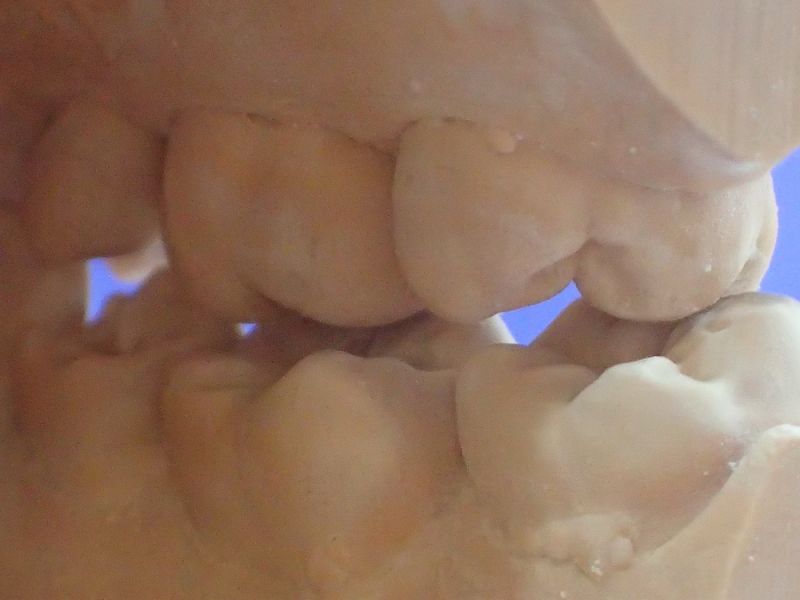

Patientin von der dänischen Grenze erhält einen adjustierten Aufbissbehelf

Obwohl die Patientin erkennbar eine gute Mundhygiene beteibt, zeigt sich im gesamten Oberkiefer und hier vor allem im Bereich der Backenzähne ein ausgeprägte und altersuntypisch weit voran geschrittener Knochenabbau.